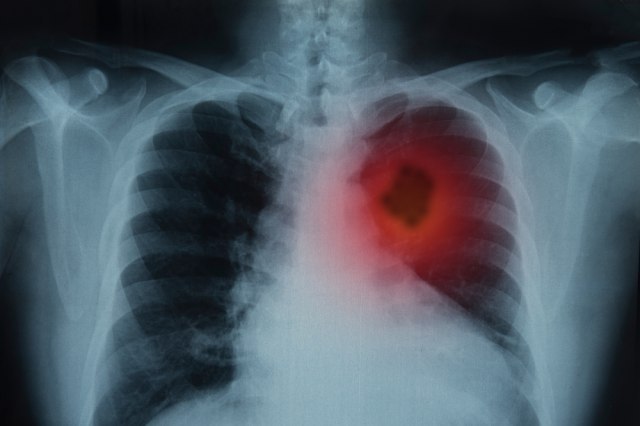

Rak pluća je jedan od najčešćih karcinoma u SAD, i to je najčešći uzročnik smrti od raka. Prema Američkom društvu za rak, više ljudi umre od raka pluća svake godine nego od raka debelog creva, dojke i prostate zajedno. Rano otkrivanje je ključno. Kao i skrining za rak pluća, za neke grupe ljudi.